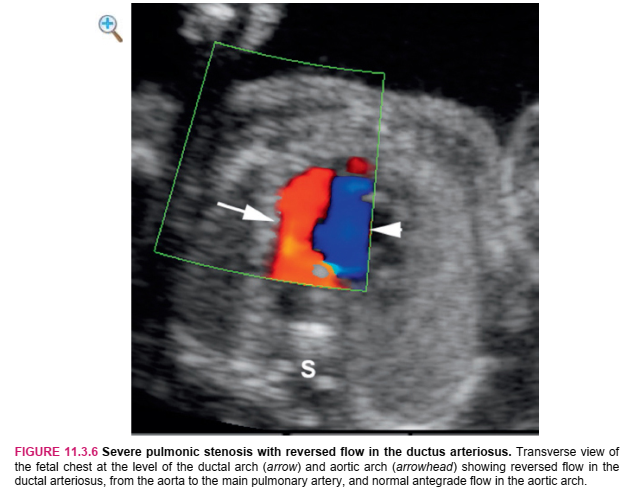

With pulmonic stenosis, there is narrowing at the level of the pulmonic valve (Figure 11.3.4). Measurement of the pulmonic valve can be compared with norms for gestational age to assess the degree of narrowing. Poststenotic dilation of the pulmonic artery may be seen in some cases of isolated pulmonic stenosis (Figure 11.3.5). With pulmonic atresia or critical pulmonic stenosis, retrograde flow may be seen in the ductus arteriosus, carrying blood from the aorta to the pulmonary arteries. The reversed flow in the ductus arteriosus is best seen on a transverse color Doppler image of both the ductal arch and the aortic arch and is diagnosed when flow in the ductal arch is in the opposite direction to flow in the aortic arch (Figure 11.3.6). Careful assessment for accompanying cardiac anomalies is warranted, especially looking for abnormalities of the tricuspid valve and ventricular septum.